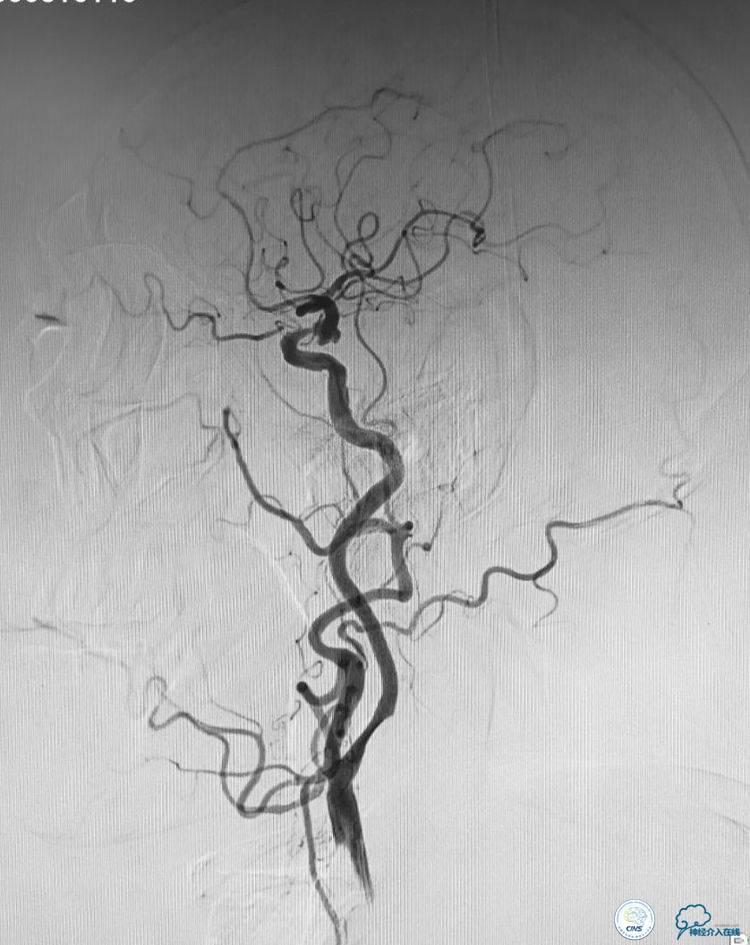

患者,男,72岁,左侧后交通未破裂宽颈不规动脉,同侧交通段有个80一90%狭窄。

1. 路途迂曲,右侧髂动脉迂曲,左颈总动脉迂曲,左颈内动脉开口狭窄50%左右。

本例手术的特点和难点:髂动脉、主动脉、颈动脉迂曲,左侧颈动脉开口有狭窄。后交通动脉瘤呈宽颈分叶状,动脉瘤近端有一个约80一90%的狭窄。